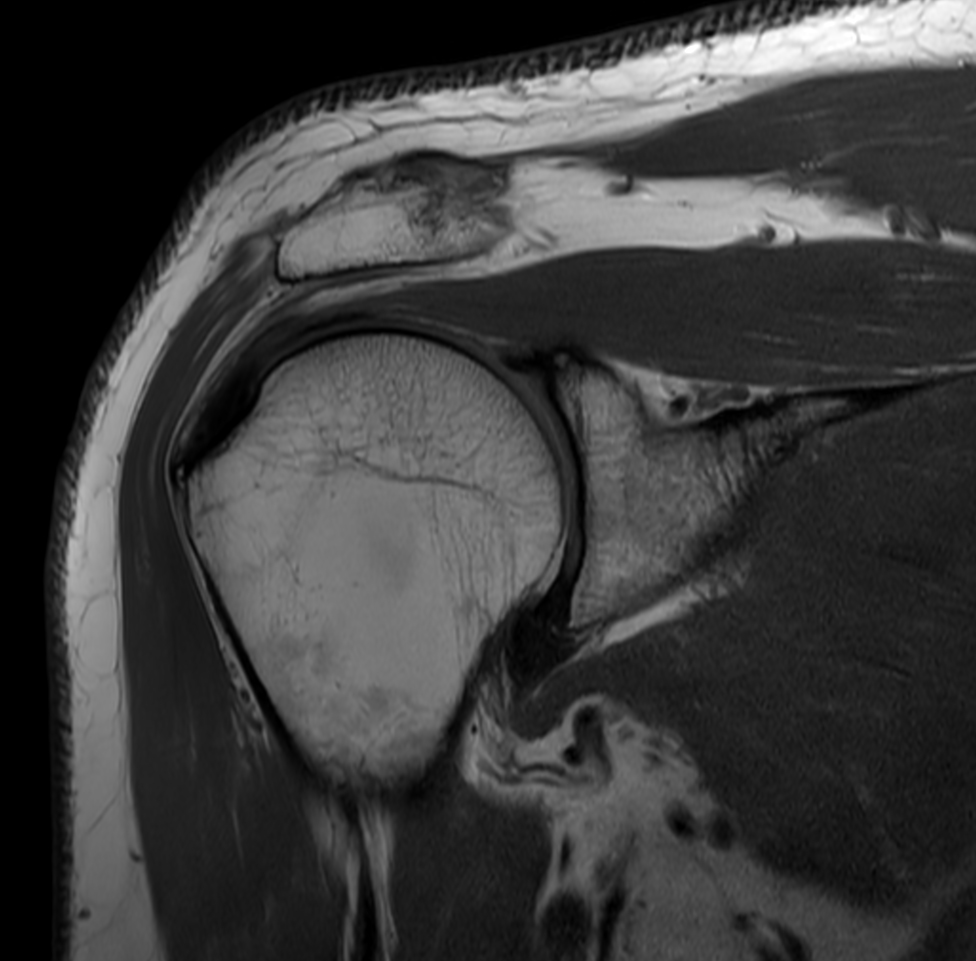

High resolution imaging with the dS 16ch Shoulder coil and Compressed SENSE